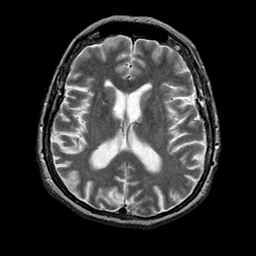

Alzheimer's disease: overlay -- Slice #14

[Home][Help][Clinical] Slice 14